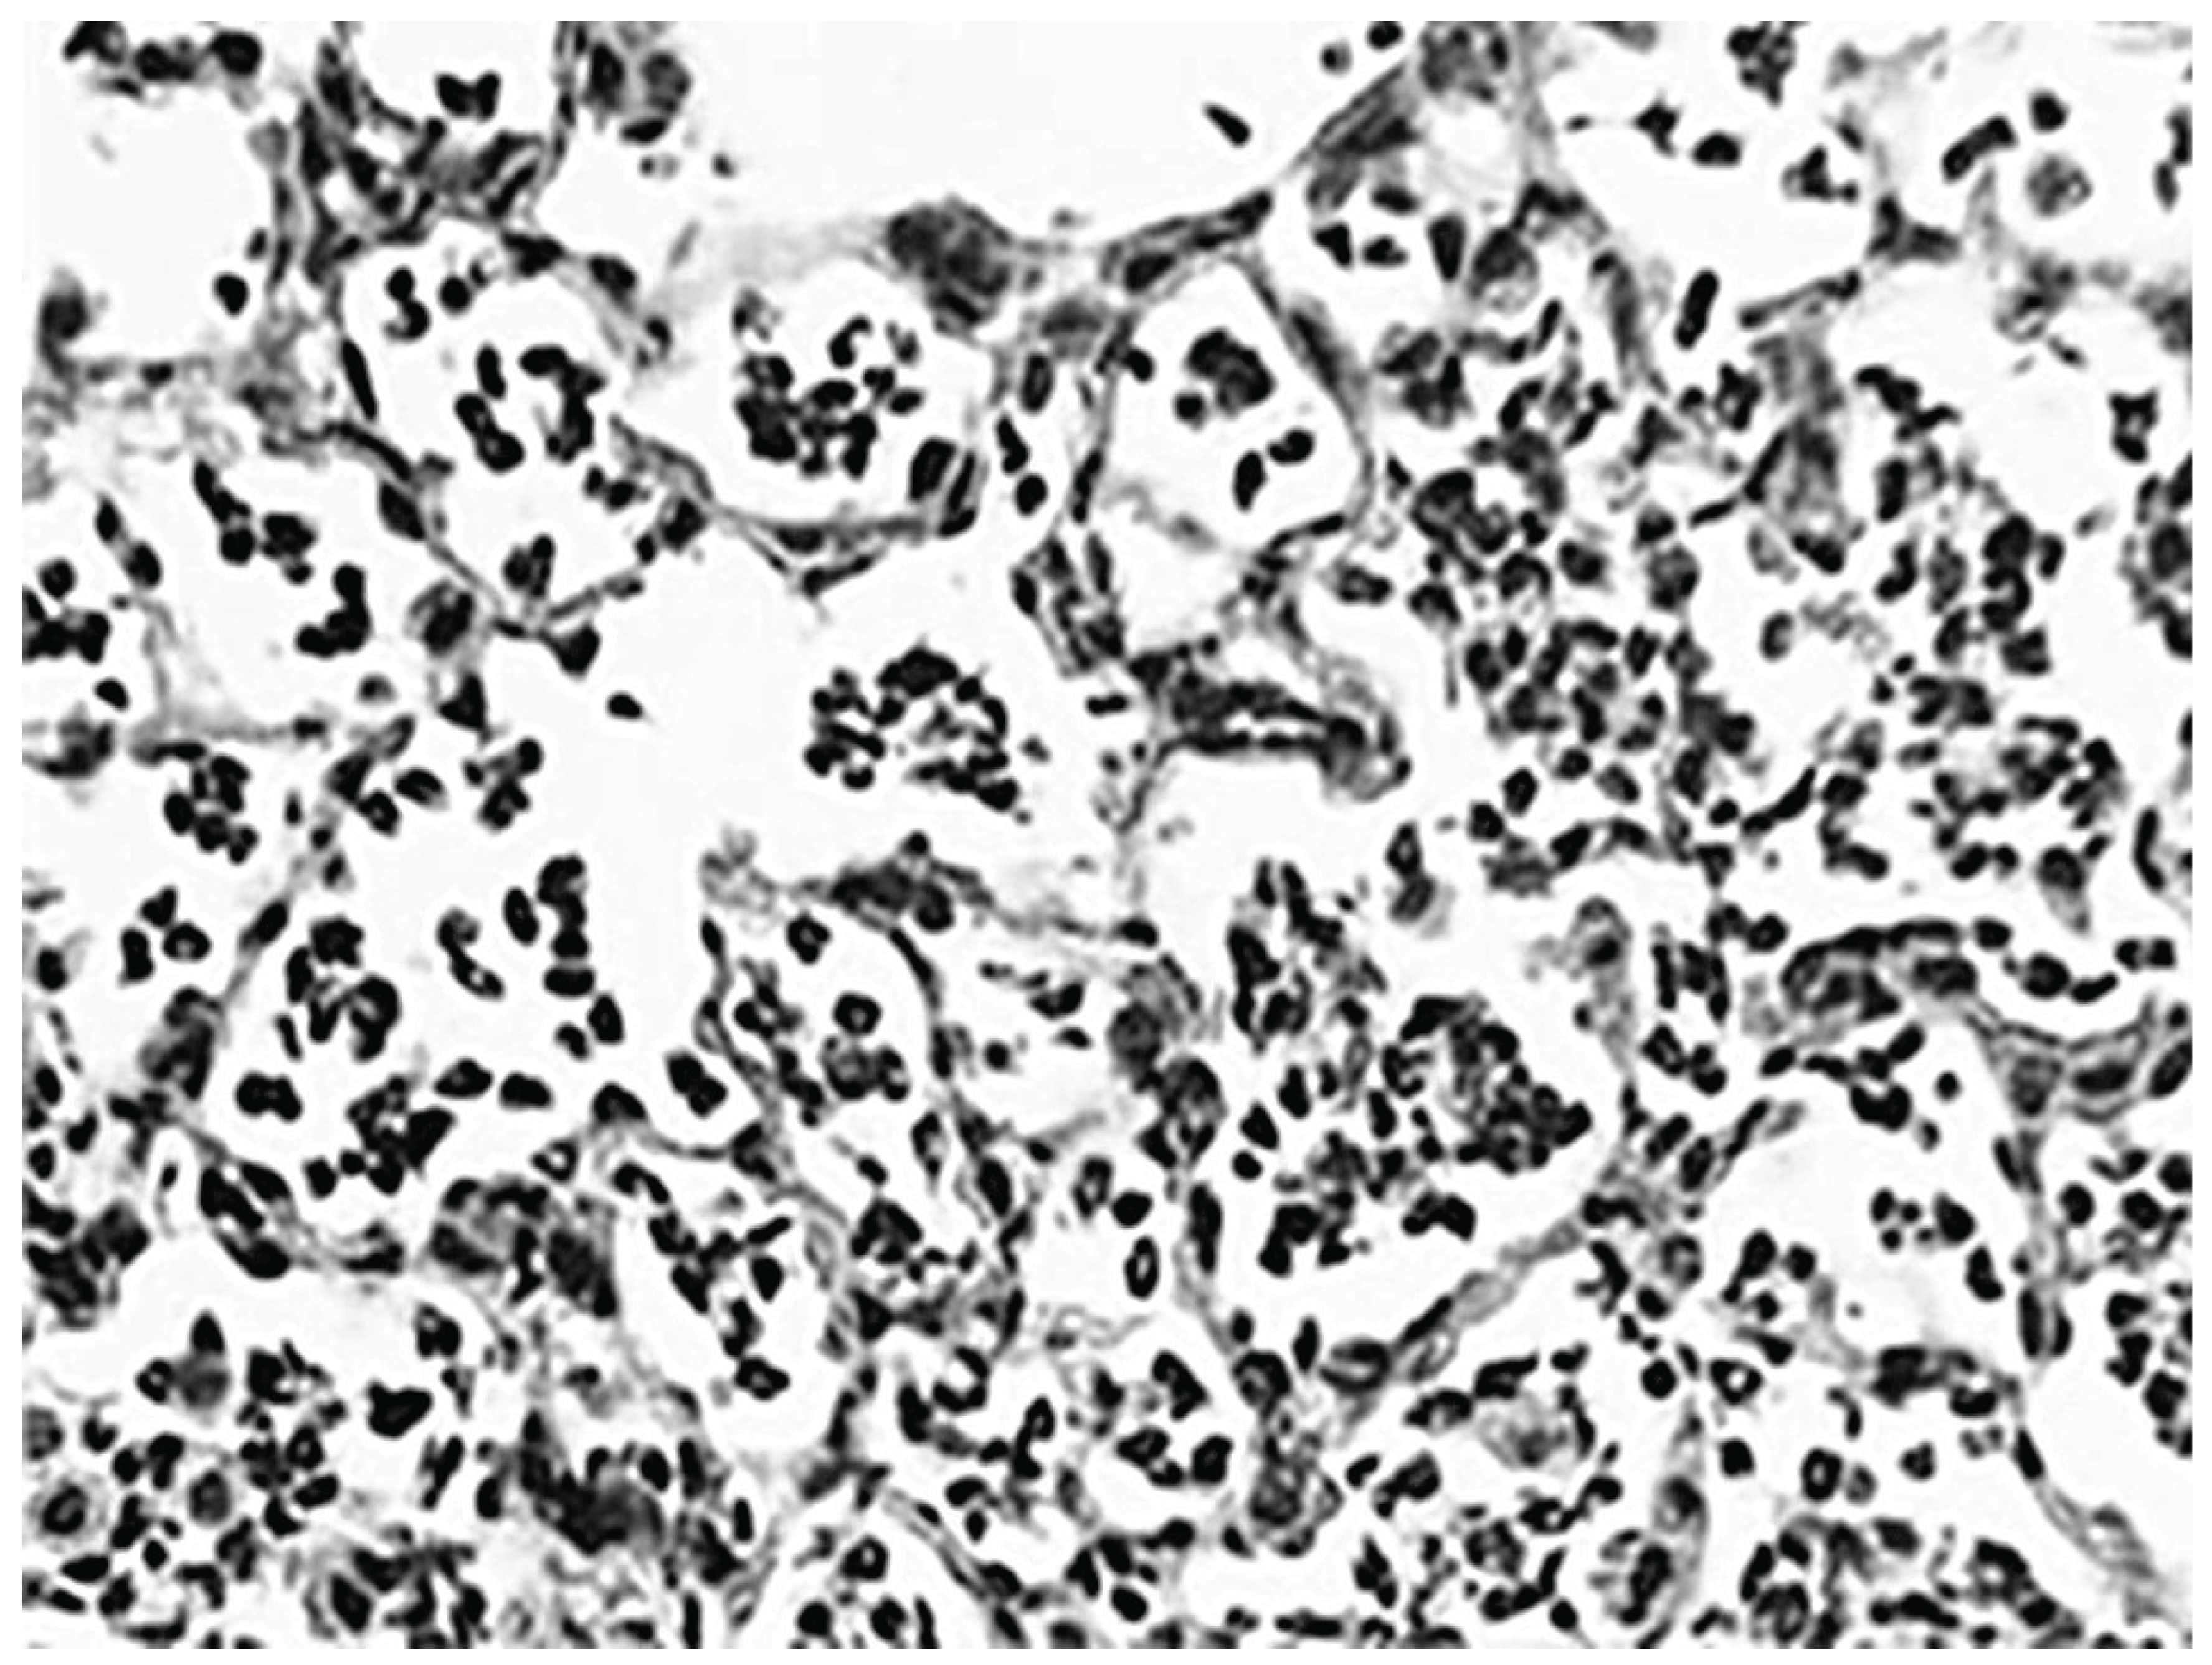

3.1. Biochemical and Morphological Features

- Cantor, J.O.; Cerreta, J.M.; Keller, S.; Turino, G.M. Modulation of Airspace Enlargement in Elastase-Induced Emphysema by Intratracheal Instalment of Hyaluronidase and Hyaluronic Acid. Experimental lung research 1995, 21(3), 423–436. [Google Scholar] [CrossRef]

- Cantor, J.O.; Cerreta, J.M.; Armand, G.; Turino, G.M. Further investigation of the use of intratracheally administered hyaluronic acid to ameliorate elastase-induced emphysema. Experimental lung research 1997, 23(3), 229–244. [Google Scholar] [CrossRef] [PubMed]